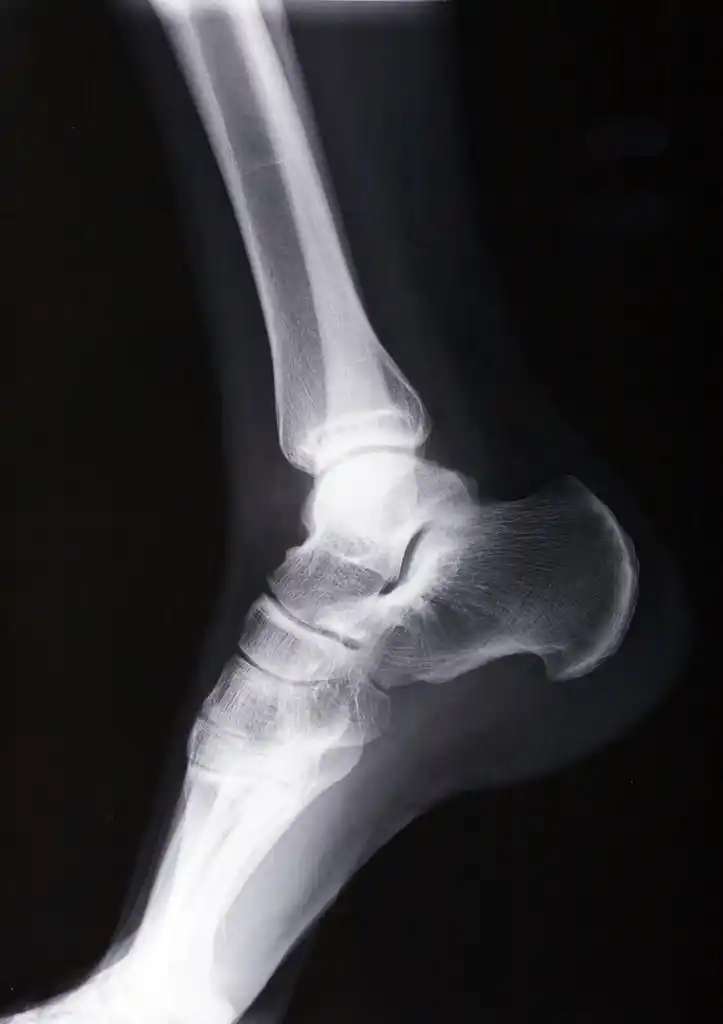

踝关节见横行骨折线又或者是这样的,急诊医生开的申请单是踝关节正侧

右脚踝 x 光片侧面扫描

请教各位:10579-右踝关节正侧位片

【读片】左踝.x [病例帖]

脚踝右侧胫骨远端骨折康复历程